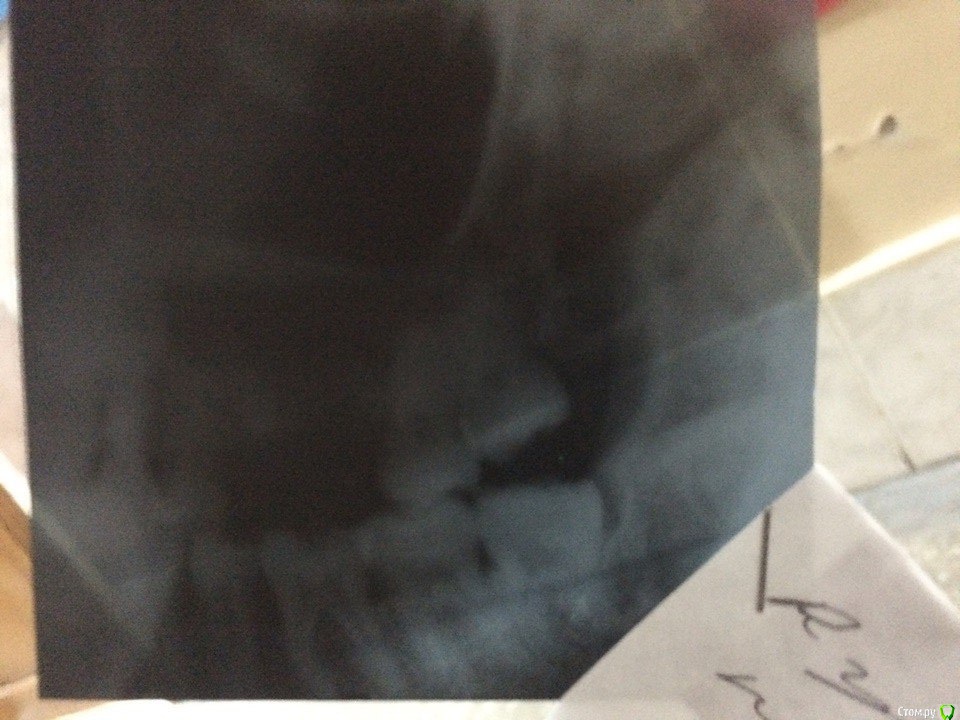

red_butler Опубликовано 30 ноября, 2016 Поделиться Опубликовано 30 ноября, 2016 Делайте Кт с захватом придаточных пазух носа. 1 Ссылка на комментарий

kyzykty1894 Опубликовано 28 декабря, 2016 Автор Поделиться Опубликовано 28 декабря, 2016 Делайте Кт с захватом придаточных пазух носа.Здравствуйте! Я сделал КТ, но никак не могу загрузить сюда Ссылка на комментарий